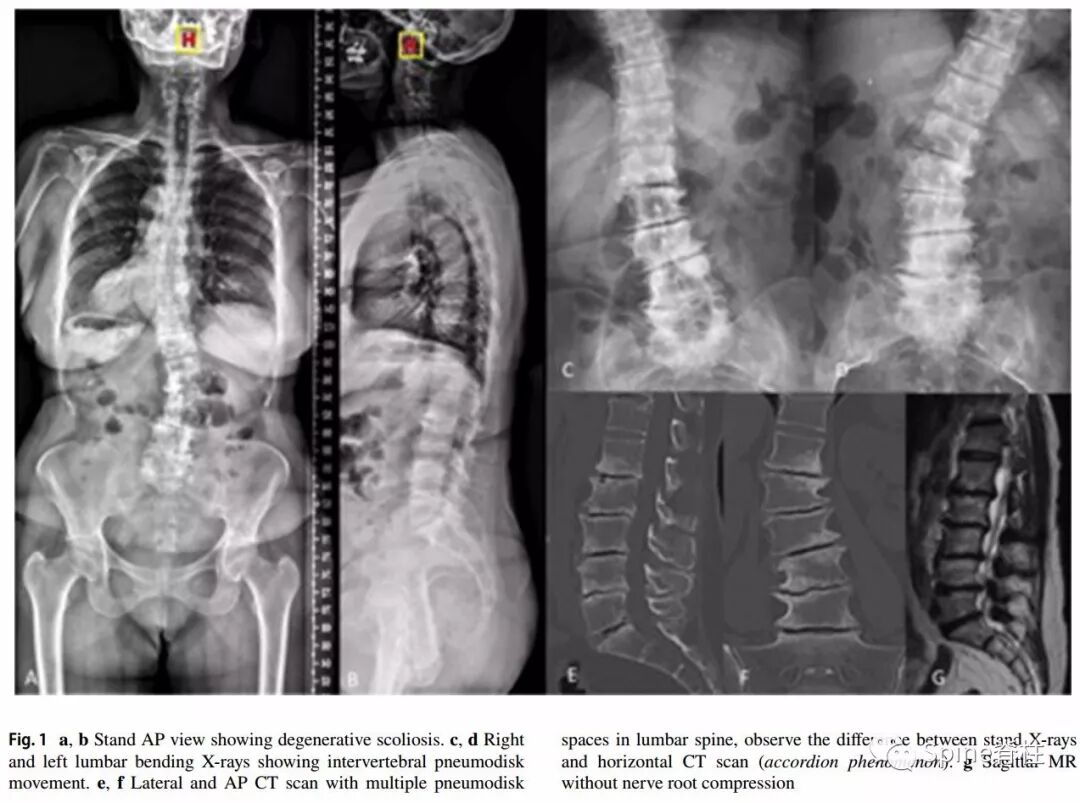

适应症:存在机械性腰痛和椎间盘真空现象的老年患者,且症状与站立位或仰卧位X片、CT中椎间盘高度的变化有关,也称之为accordion phenomenon(手风琴现象)。1个或多个节段的脊柱畸形或退行性椎体滑脱且因高手术风险、不能耐受开放手术的患者。

一例78岁的老年患者,慢性腰痛1年(VAS 7分),活动后加重,卧床后减轻,严重影响生活质量,但无下肢放射痛,无四肢运动和感觉障碍。

-

术前影响资料可见退行性侧凸伴多节段椎间盘真空征。

典型的手风琴现象

左图为站立位X片,右图为仰卧位CT平扫。站立位负重时的椎间盘与仰卧位(不负重)椎间盘塌陷程度不同,且侧凸角度也不同(分别为25°和14°)。